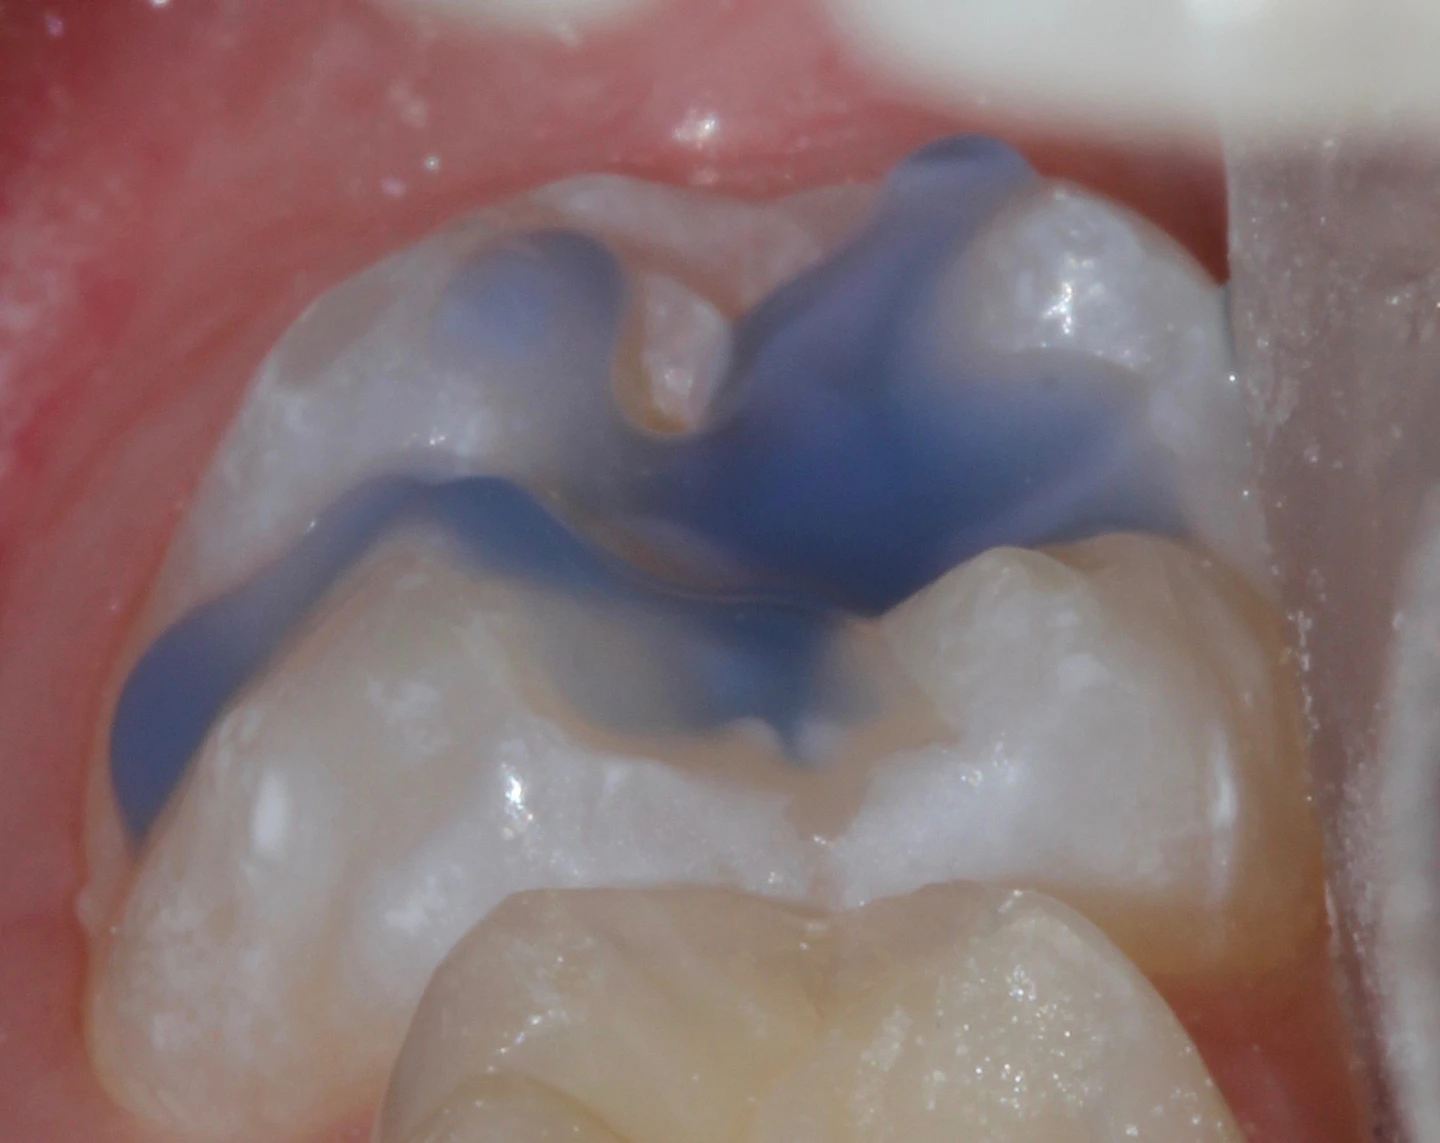

Acid etching, dental / adverse effects* burns, chemical / etiology* facial injuries / etiology* Potential hazard of acid burns to the skin during procedures using dental etching. Sir, we were interested to read the letter about a facial burn caused by acid etch ( bdj 2014; When desiccated, a surface that has been etched appears chalky white or frosted (figure 6.1c). Ceramic surfaces were exposed to acid etching for four different time intervals with 5% hydrofluoric acid gel for dental use (ips. A number of materials can be used for etching, but the most. Acid etch creates microscopic spaces in enamel (increasing surface roughness) into which the bonding agent/adhesive can flow, aiding the bonding process (micromechanical retention). Phosphoric acid, sometimes also called orthophosphoric acid, is a substance that is used frequently in the practice of dentistry,. Acid etching is used to successfully bond existing tooth structure with a prosthetic or repair, whether it be a crown, a filling or a.